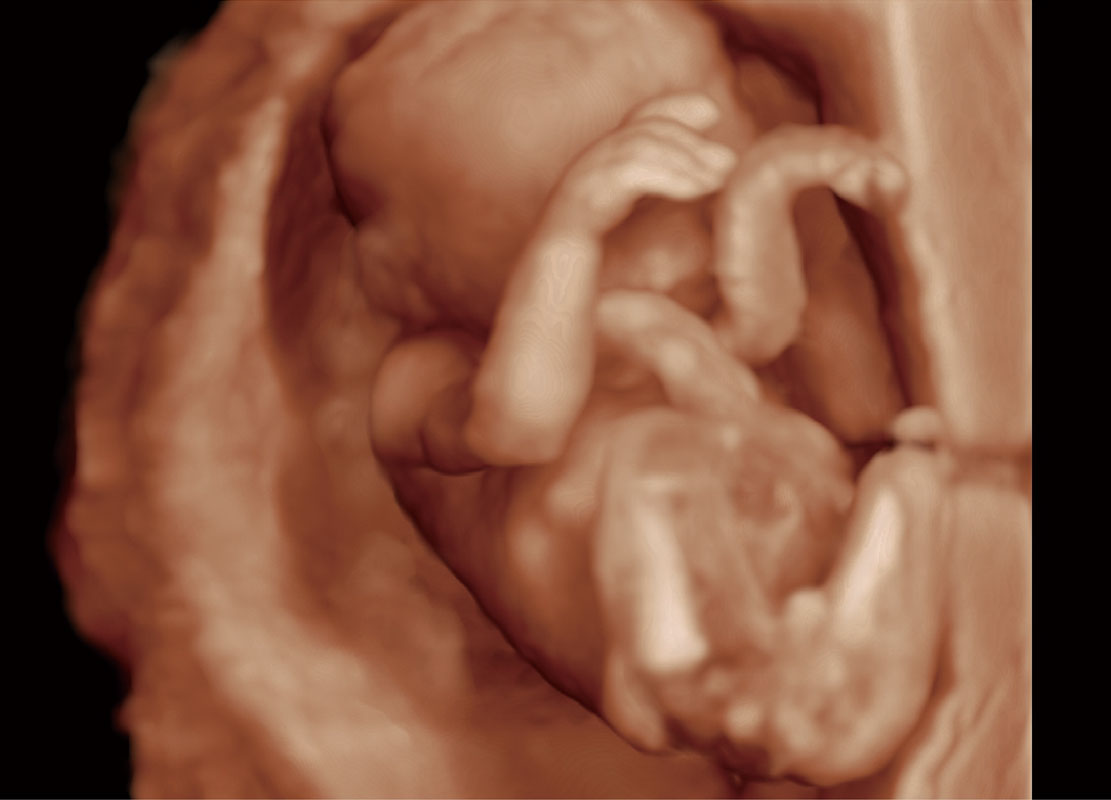

P60在胎兒早孕期超聲篩查中為您帶來(lái)優(yōu)異的圖像質(zhì)量。

高分辨率容積成像-早孕胎兒

光影成像-孕囊